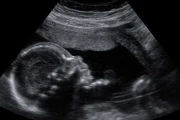

Mediante un video, Verónica relató que el 1 de diciembre de 2015, su hija, Keila Jones, de 8 semanas de embarazo acudió al hospital El Maitén para pedir ayuda a una asistente social al no saber cómo afrontar su situación.

La joven fue derivada para someterse a una "Interrupción Legal del Embarazo" utilizando el mecanismo previsto por el protocolo de "abortos no punibles" establecido por la ex presidente Cristina Kirchner en 2015.

Le administraron misoprostol y la dejaron en observación. Después de un rato, Keila llamó por teléfono a su mamá desde el hospital.